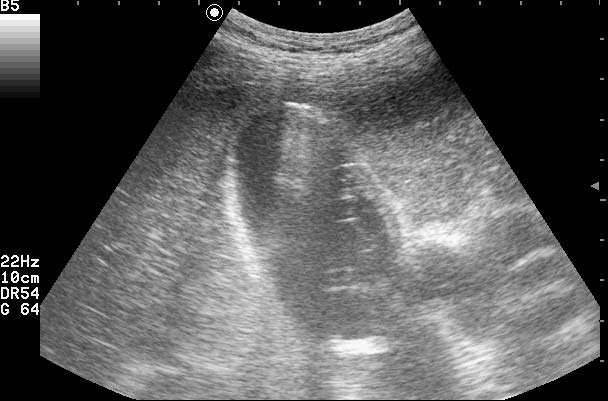

Эмпиема ЖП. Перивезикулярный абсцесс

Пожилая женщина с болями в правом подреберье, высокой температурой.

Газ находится вне пузыря- в его ложе

3 попытка- Острый эмфизематозный холецистит. Эмпиема ЖП. Паравезикулярный абсцесс (других идей пока нет)

Вся фишка в том, что жидкость - гной - на УЗИ можно не увидеть, настолько тонким может быть ее слой. НО - о ее/его наличии указывает ГАЗ ВНЕ ПУЗЫРЯ.besliu писал(а):Покажите,пожалуйста,стрелочкой,где паравезик.абсцесс,что-то не вижуСпасибо.

Напомню, что все случаи представленные в разделах "Загадки" и "Архив" - верифицированы при оперативном вмешательстве, либо гистологически, либо с применением других методов.